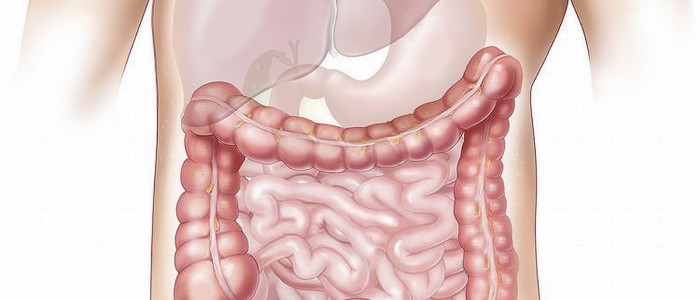

Rakovina tlustého střeva

11. 4. 2017 Připravili jsme pro vás seriál o nemocech, tentokrát na téma rakovina tlustého střeva. Po krátkém popisu nemoci předložíme možnosti léčby klasickou me... zobrazit článek

Zácpa

23. 11. 2016 Připravili jsme pro vás seriál o nemocech, tentokrát na téma zácpa. Po krátkém popisu nemoci předložíme možnosti léčby klasickou medicínou, možnosti l... zobrazit článek